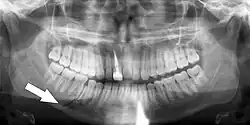

Nondisplaced fracture of the mandible

Panoramic radiography

Panoramic radiographs are tomograms where the mandible is in the focal trough and show a flat image of the mandible. Because the curve of the mandible appears in a 2-dimensional image, fractures are easier to spot leading to an accuracy similar to CT except in the condyle region. In addition, broken, missing or malaligned teeth can often be appreciated on a panoramic image which is frequently lost in plain films. Medial/lateral displacement of the fracture segments and especially the condyle are difficult to gauge so the view is sometimes augmented with plain film radiography or computed tomography for more complex mandible fractures.